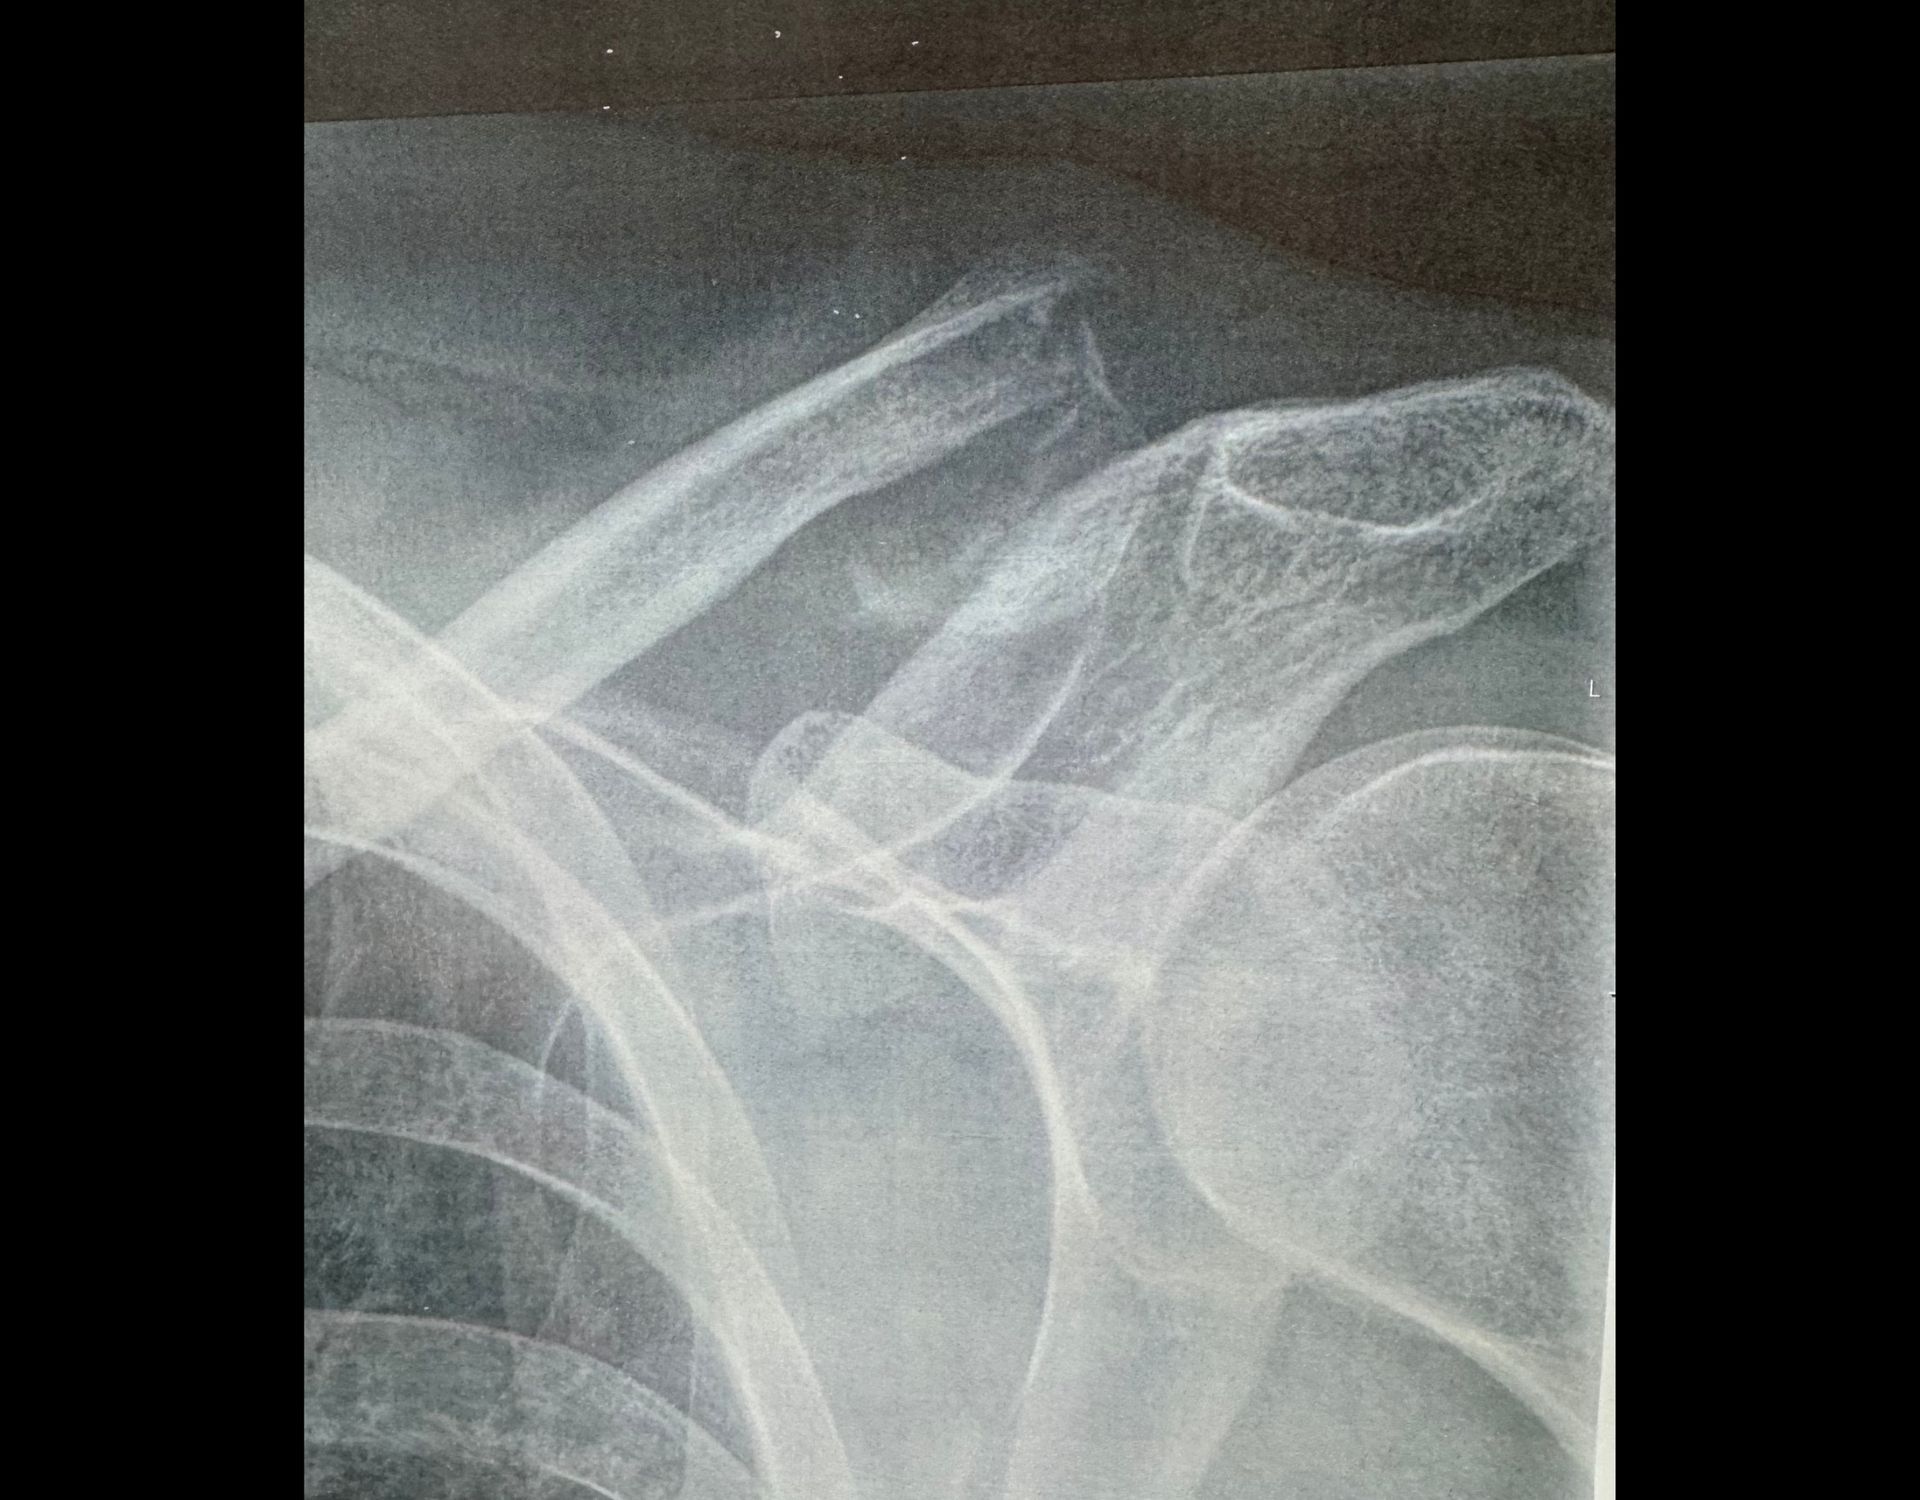

Στα ασταθή περιφερικά κατάγματα της κλείδας, ιδίως όταν το περιφερικό τεμάχιο είναι μικρό, πολυτεμαχισμένο ή δεν “κρατάει” καλά βίδες, η hook plate έχει το πλεονέκτημα ότι δίνει έμμεση σταθεροποίηση και συχνά επιτρέπει αξιόπιστη πώρωση χωρίς να χρειάζεται μεγάλη αγορά οστού στο έξω τμήμα. Αυτός είναι και ο βασικός λόγος που εξακολουθεί να χρησιμοποιείται.

In unstable distal clavicle fractures—particularly when the distal fragment is small, comminuted, or does not allow secure screw fixation—the hook plate offers the advantage of indirect stabilization and often enables reliable healing without substantial bone purchase in the lateral fragment.